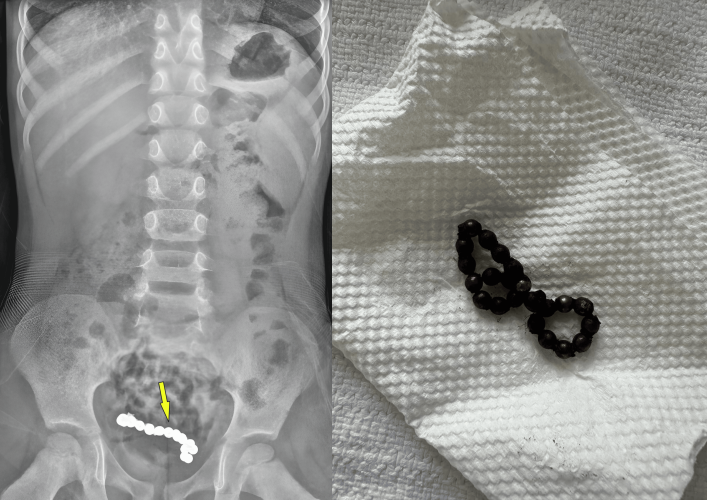

1년간 복통을 호소해 온 4세 남아의 뱃속에서 자석 조각 22개가 발견됐다. 큐레우스 캡처

복부 엑스레이(X-ray)와 컴퓨터단층촬영(CT) 결과, 하복부에서 사슬처럼 연결된 둥근 이물질 여러 개가 관찰됐다.

의료진은 복강경 수술을 진행했다. A 군의 배에서는 22개의 자석 조각이 나왔다. 자석들은 서로 붙어 있는 상태였다.

자석의 인력으로 A 군의 장 일부가 괴사해 장의 약 15㎝를 절제했다.